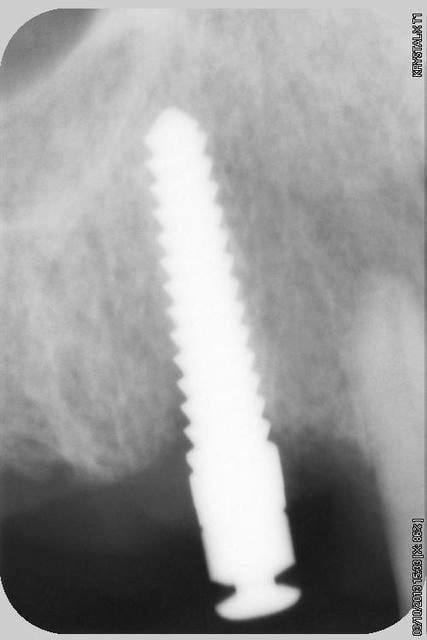

quelques radios.

oui, bien sur ce sont des Tatum D1 en bas et D4 en haut